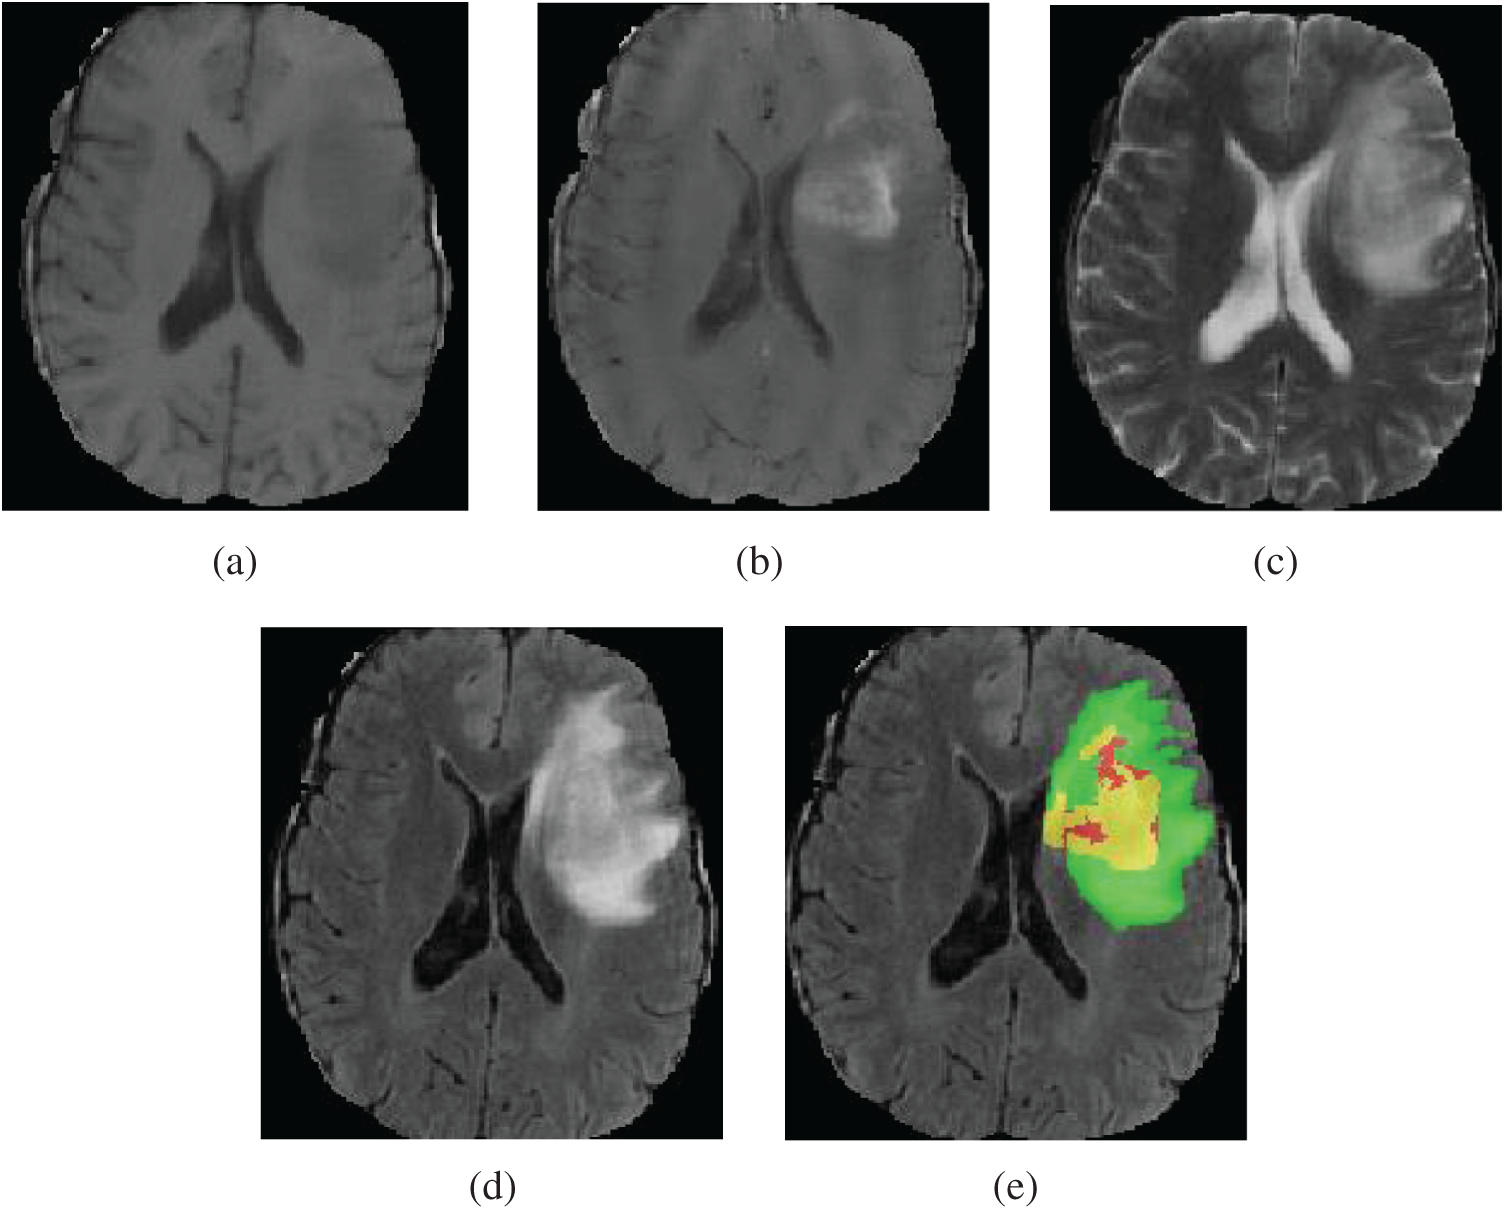

Gliomas are the most widespread malignant brain tumor, accounting for about 70% of primary malignant brain tumors [1,2]. In the light of the World Health Organization (WHO) classification of gliomas, gliomas can be classified into high grade gliomas (HGG) and low grade gliomas (LGG). LGG growth rate is relatively slow and has low malignant degree of tumor and better prognosis of patients. HGG are malignant and more aggressive with faster growth rate and relatively poor prognosis effect. Generally, after diagnosis, the survival time of patients having HGG is about 2 years [3,4]. Therefore, for patients with brain tumor, early detection, diagnosis and treatment is of great value to improve the treatment effect [5,6]. Magnetic resonance imaging (MRI) has developed into the most popular imaging examination for the diagnosis of gliomas in clinical medicine, because it can obtain high-resolution and clear contrast images of brain tissues [7]. According to the degree of invasion, prognosis and other factors, the gliomas show the following sub-regions: peritumoral edema, necrotic core, enhancing tumor core and non-enhancing tumor core [2,3,8]. Multimodal MRI scans are used to reflect the various histological sub-regions by different intensity distribution [9]. The four MRI modalities are T1 weighted (T1), T1 weighted with post-contrast (T1Gd), T2 weighted (T2) and fluid attenuated inversion recovery (FLAIR) [3,5]. Each modality provides different biological information of tumors, which can clearly reflect the internal structure of gliomas. Four MRI modalities axial slices and ground truth segmentation of a patient data (named “BraTS19_TCIA01_201_1”) on the BraTS2019 training dataset is shown in Fig. 1. T2 and FLAIR clearly reflect the whole tumor area, T2 reflects the tumor core and T1Gd reflects the enhancing tumor. Accurate tumor segmentation of MRI modalities is a critical step in clinical diagnosis and efficacy evaluation. Segmentation of MRI brain tumors is difficult, because of the variable location, shape, size and the poorly contrasted boundary with brain normal tissues. Manual segmentation of brain tumors in MR images is time-consuming and is easy to be influenced by the subjective judgment of experts. Therefore, semi-automatic and automatic segmentation of brain tumors have been the important research topics in medical image analysis in recent 20 years, bringing about many kinds of brain tumor segmentation approaches.

Figure 1: Four MRI modalities axial slices of a patient data from the BraTS2019 training dataset. From (a) to (d) are T1, T1Gd, T2 and FLAIR. (e) The ground truth segmentation, that green indicates edema, yellow indicates enhancing tumor, red indicates non-enhancing tumor and necrotic